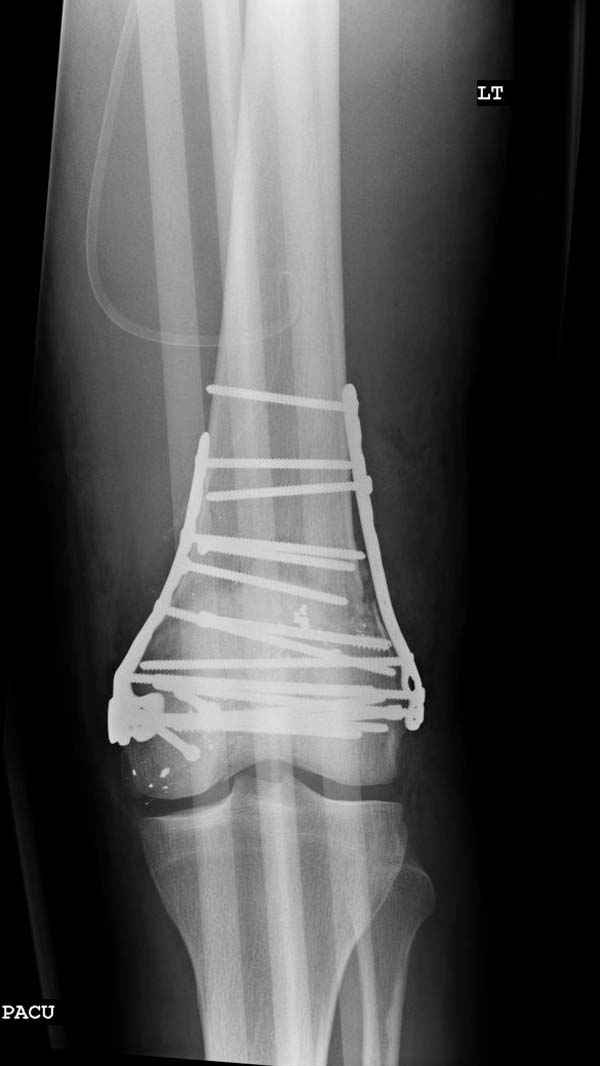

Красиво и быстро?! - две пластины + 18 шурупов.

Идеальная репозиция?! -На снимочке A-P проeкции видна "зазубрина" по суставной поверхности, латеральный снимок - тоже не идеально.

Сустав не дренировался, но медиально перед закрытием раны под фасцией уложен дренаж Hemovac, который удален через 24 часа.

Если больной продолжает оставаться в больнице, то после удаления дренажа назначаются реабилитация-разработка сустава на CPM (аппарат для принудительной разработки суставов) с увеличением амплитуды на нарастание.

Хотя многие не дожидаясь СПМ уходят домой, после прохождения теста для применения костылей, (т.е. другими словами, как только пациент становится способным передвигаться с применением дополнительных средств опоры).